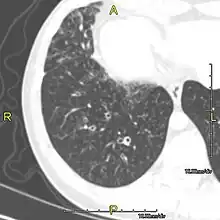

Around 80% of people with primary ciliary dyskinesia experience respiratory problems beginning within a day of birth. Many have a collapsed lobe of the lung and blood oxygen low enough to require treatment with supplemental oxygen.[1] Within the first few months of life, most develop a chronic mucus-producing cough and runny nose.[1] The main consequence of impaired ciliary function is reduced or absent mucus clearance from the lungs, and susceptibility to chronic recurrent respiratory infections, including sinusitis, bronchitis, pneumonia, and otitis media. Progressive damage to the respiratory system is common, including progressive bronchiectasis beginning in early childhood, and sinus disease (sometimes becoming severe in adults). However, diagnosis is often missed early in life despite the characteristic signs and symptoms.[2] In males, immotility of sperm can lead to infertility, although conception remains possible through the use of in vitro fertilization, there also are reported cases where sperm were able to move.[8] Trials have also shown that there is a marked reduction in fertility in females with Kartagener's syndrome due to dysfunction of the oviductal cilia.[9]

Many affected individuals experience hearing loss and show symptoms of otitis media which demonstrates variable responsiveness to the insertion of myringotomy tubes or grommets. Some patients have a poor sense of smell, which is believed to accompany high mucus production in the sinuses (although others report normal – or even acute – sensitivity to smell and taste). Clinical progression of the disease is variable, with lung transplantation required in severe cases. Susceptibility to infections can be drastically reduced by an early diagnosis. Treatment with various chest physiotherapy techniques has been observed to reduce the incidence of lung infection and to slow the progression of bronchiectasis dramatically. Aggressive treatment of sinus disease beginning at an early age is believed to slow long-term sinus damage (although this has not yet been adequately documented). Aggressive measures to enhance clearance of mucus, prevent respiratory infections, and treat bacterial superinfections have been observed to slow lung-disease progression. The predicted incidence is 1 in approximately 7500.[10]

When accompanied by the combination of situs inversus (reversal of the internal organs), chronic sinusitis, and bronchiectasis, it is known as Kartagener syndrome[3] (only 50% of primary ciliary dyskinesia cases include situs inversus).[11]